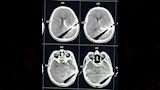

نجح فريق طبي بمستشفى طوارئ قصر العيني في إجراء تدخل جراحي بالغ الدقة والتعقيد؛ لإنقاذ حياة مريض يبلغ من العمر 18 عامًا، وصل إلى المستشفى في حالة حرجة إثر إصابة نافذة بالرأس بآلة حادة اخترقت عظام الجمجمة واستقرت داخل أنسجة المخ.

وكان المستشفى قد استقبل الحالة في تمام الساعة الحادية عشرة صباحًا؛ حيث كان المريض يعاني اضطرابًا شديدًا بدرجة الوعي نتيجة الإصابة الخطيرة، وعلى الفور جرى إدخاله إلى غرفة الإصابات المتعددة، حيث تم التعامل العاجل مع الحالة وفقًا للبروتوكولات الطبية المعتمدة للحالات الحرجة، وتقديم الإسعافات الأولية اللازمة، مع مناظرة الحالة من قِبل فرق طبية متعددة التخصصات، وإجراء الفحوصات العاجلة من أشعة وتحاليل دقيقة لتقييم الإصابة وتحديد خطة التدخل.

وفي أقل من ساعة من وصول المريض، ووفقًا لأعلى معايير الاستجابة السريعة في التعامل مع حالات الطوارئ الحرجة، تم نقل المريض إلى غرفة إنقاذ الحياة؛ حيث جرى تجهيزه فورًا لإجراء تدخل جراحي عاجل بواسطة فريق جراحة المخ والأعصاب بمستشفى طوارئ قصر العيني.

وتضمن التدخل الجراحي استخراج الآلة الحادة من داخل أنسجة المخ وعظام الجمجمة بدقة متناهية، مع اتخاذ جميع الإجراءات الجراحية اللازمة للحفاظ على سلامة الأنسجة الحيوية بالمخ والسيطرة الكاملة على النزيف ومنع حدوث مضاعفات خطيرة.